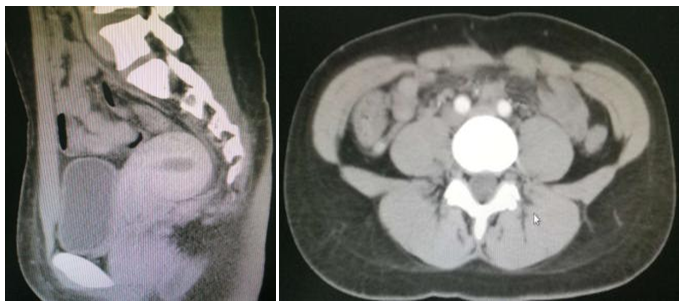

Postoperative pathology of the right ovary revealed serous borderline tumors and corpus luteum cysts. (Figure 2) (Figure 3) The right fallopian tube was negative for malignancy. An endometrial specimen showed early secretory stage but no tumor involvement. The uterine surface nodules were determined to be leiomyoma. Omentum and bilateral lymph nodes were negative for metastasis. Therefore, with SBT limited to the surface of one ovary it was staged as 1C2, which is defined as a tumor that is on the outer surface of at least one of the ovaries or fallopian tubes or the capsule has ruptured before surgery.8

Figure 2 Pathology: Gross appearance of right ovarian tumor with papillary surface: Gray red tissue measuring 1cm X 0.7cm X 0.4cm

Figure 3 Pathology slide showing borderline serous tumor of right ovary.